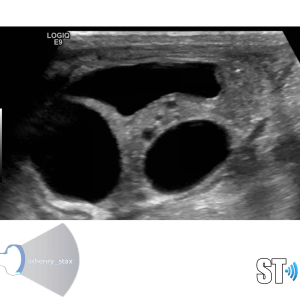

Renal Cystic Disease

Renal cysts are very common and as a sonographer you’ll encounter them frequently in the pediatric and adult populations. Approximately 50% of people who are 50 years and older have simple kidney cysts. The majority of parenchymal cystic lesions are simple epithelial cysts. They have thin walls, are anechoic, good through transmission. They can have thin septations or internal debris(5%) these may require follow up. Chronically some can develop calcifications on their walls.

Simple cysts

Cysts are non functioning parts of the kidney. Simple cysts typically pose no health problems. Simple cysts are often found incidentally when the patient is undergoing a procedure for some other complaint. To meet the criteria for cysts the lesion should be

- Round or oval

- Thin wall

- Anechoic

- Good through transmission (posterior acoustic enhancement)